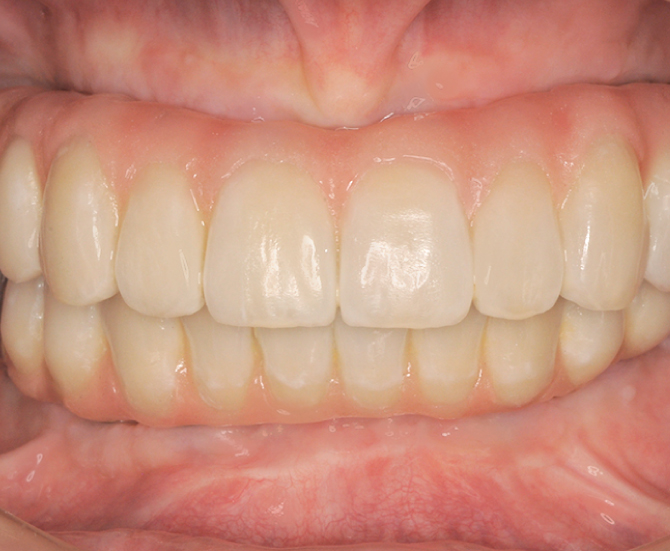

とびきり美しい上部構造

ただ治すのではなく、美しく治す。しかも、とびっきり美しく治すことにこだわっています。そのため、数々の賞を受賞する腕の良い歯科技工士と連携して歯をデザインしています。

短期間で劇的に見た目改善できる

しっかり何でも噛めるようになる